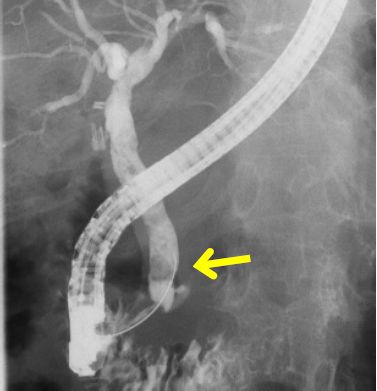

胆膵疾患(内視鏡・化学療法)

総胆管結石(写真①)には内視鏡的胆膵管造影検査(ERCP)を行い、結石は必要に応じて砕石(バスケットを用いて石を砕くこと)して小さくし、バスケットまたはバルーンで採石(写真②③④)を行います。胆管炎がある場合はまずはステントを留置して炎症を改善させた後に採石を行います。

膵癌・胆管癌・胆嚢癌などの悪性疾患については、外科治療や化学療法を行います。胆膵領域には胆管、膵管など重要な管や臓器があるため、ERCPでステントの留置を行いつつ、外科、消化器内科、腫瘍内科と連携して腫瘍の治療を行います。